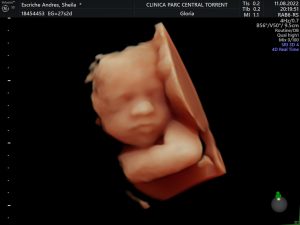

En este periodo podréis apreciar el crecimiento de vuestro bebé, incluye:

Periodo ideal para ver la carita de vuestro bebé. ¿A quién se parecerá?

Video evolución del feto en 5D